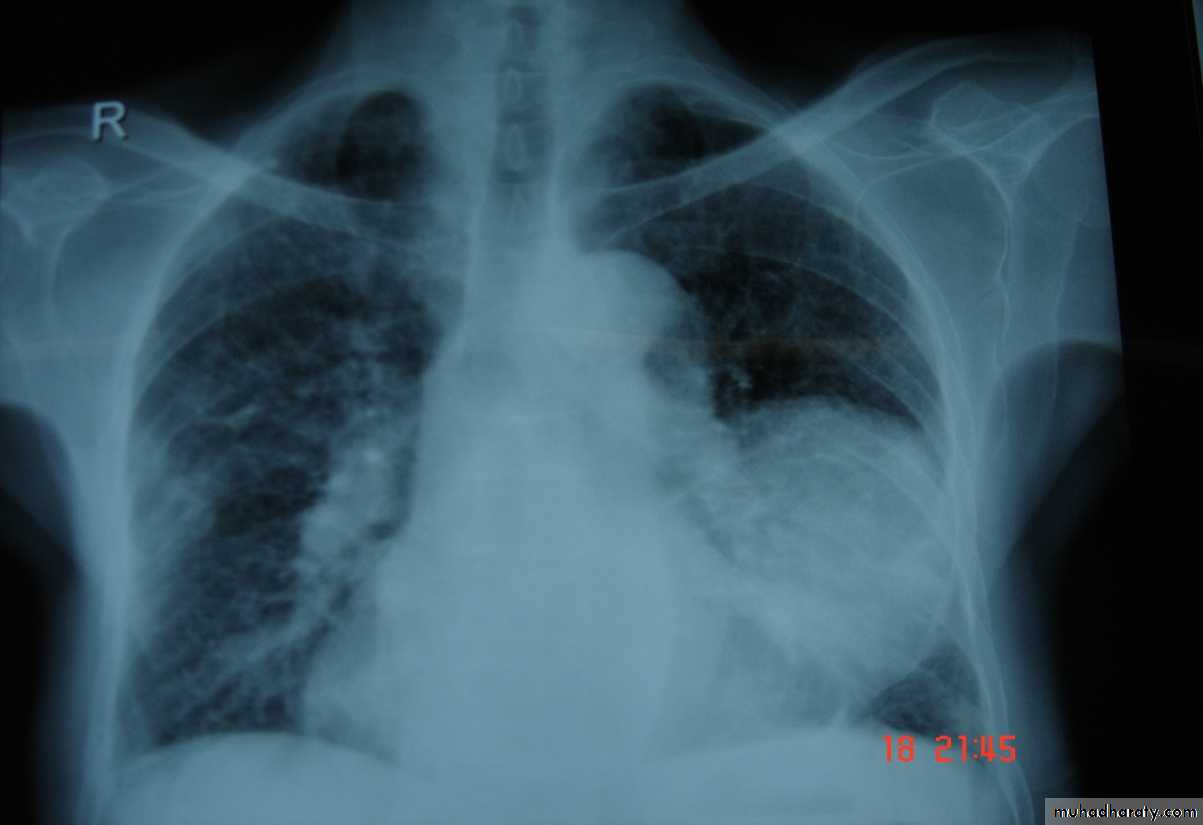

Bronchogenic Ca. cavitory lesion

• Pathology :-A-Central type is the commonest (75%).It arises in one of the main bronchi or their primary division leading to bronchial obstruction with secondary changes in the lung such as atelectasis .B-Peripheral type (25%) arises from the smaller bronchi and remains symptom less for long time .

Histologically Squamous cell Ca (SCC) 60% , smoker , centrally located ,metastasizes to mediastinal & supraclavicular LN . Adenocarcinoma (15% ) , located peripherally , more in women .Tends to metastasizes to the liver , brain ,bone & adrenals in addition to the LN Undifferentiated carcinoma (oat) cell carcinoma and large cell carcino(20-30%) which includes small cell Ca Alveolar cell carcinoma , located peripherally ,metastasizes to the liver and adrenalsRecent classification..Non small & small cell carcinoma

• Chest X-ray ,CT chest ..